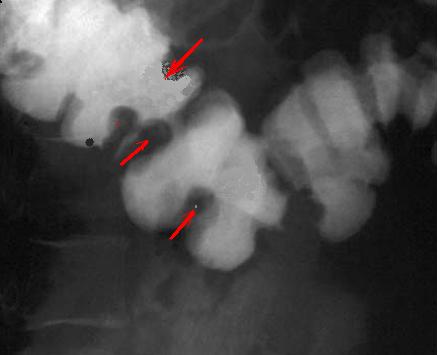

Image radiologique ASP

d'une colite ischemique : Image empreinte en

doigtier sur le colon trans verse et colon

descendant |

Image de aerique du colon et

image en empreinte de pouce ( fleche noire ) . du

colon transverse et colon descendant |